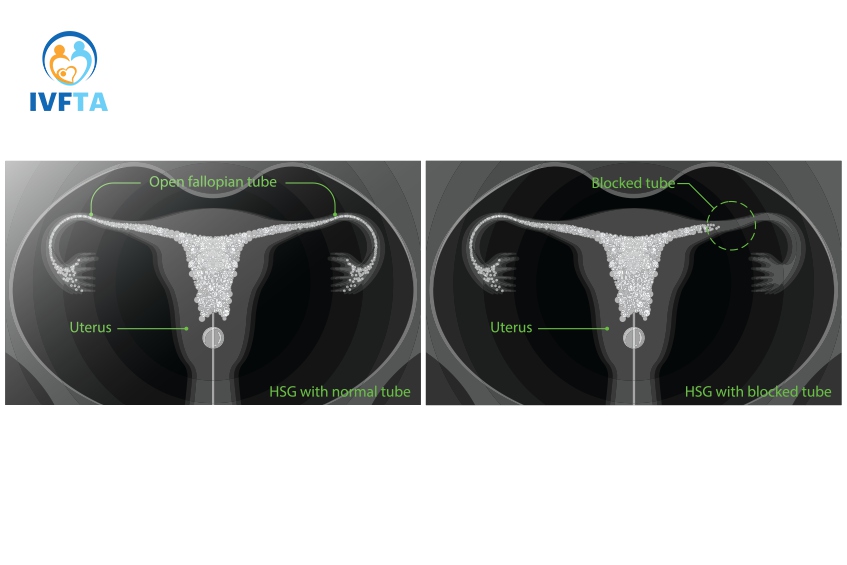

Chụp X-quang tử cung vòi trứng hay còn gọi là chụp HSG, là một thủ thuật y tế sử dụng tia X để chụp ảnh tử cung và vòi trứng. Trong quá trình này, bác sĩ sẽ bơm một chất lỏng có chứa chất cản quang (thường là một thuốc chứa iot) vào tử cung và vòi trứng, sau đó chụp X-quang để kiểm tra xem liệu có bất thường gì không. Với kỹ thuật chụp X-quang này, bác sĩ có thể:

Chụp X-quang tử cung vòi trứng đóng vai trò quan trọng trong chẩn đoán và điều trị các bệnh lý về tử cung và vòi trứng, cũng như trong việc đánh giá nguyên nhân gây vô sinh ở nữ giới. Thông qua việc kiểm tra hình dạng và tình trạng thông suốt của tử cung và vòi trứng, bác sĩ có thể phát hiện các bất thường như tắc nghẽn, dị dạng, u xơ… hoặc dính buồng tử cung sau can thiệp phẫu thuật, thủ thuật… là nguyên nhân gây vô sinh ở nữ giới.

Kết quả của chụp X-quang tử cung vòi trứng thường được coi là một thông tin đáng tin cậy trong việc đánh giá tình trạng của tử cung và vòi trứng. Thông qua hình ảnh từ chụp HSG, bác sĩ có thể nhận diện các vấn đề như tắc nghẽn vòi trứng, bất thường hình dạng tử cung, hay thậm chí là những dấu hiệu của bệnh lý như u nang hoặc polyp.